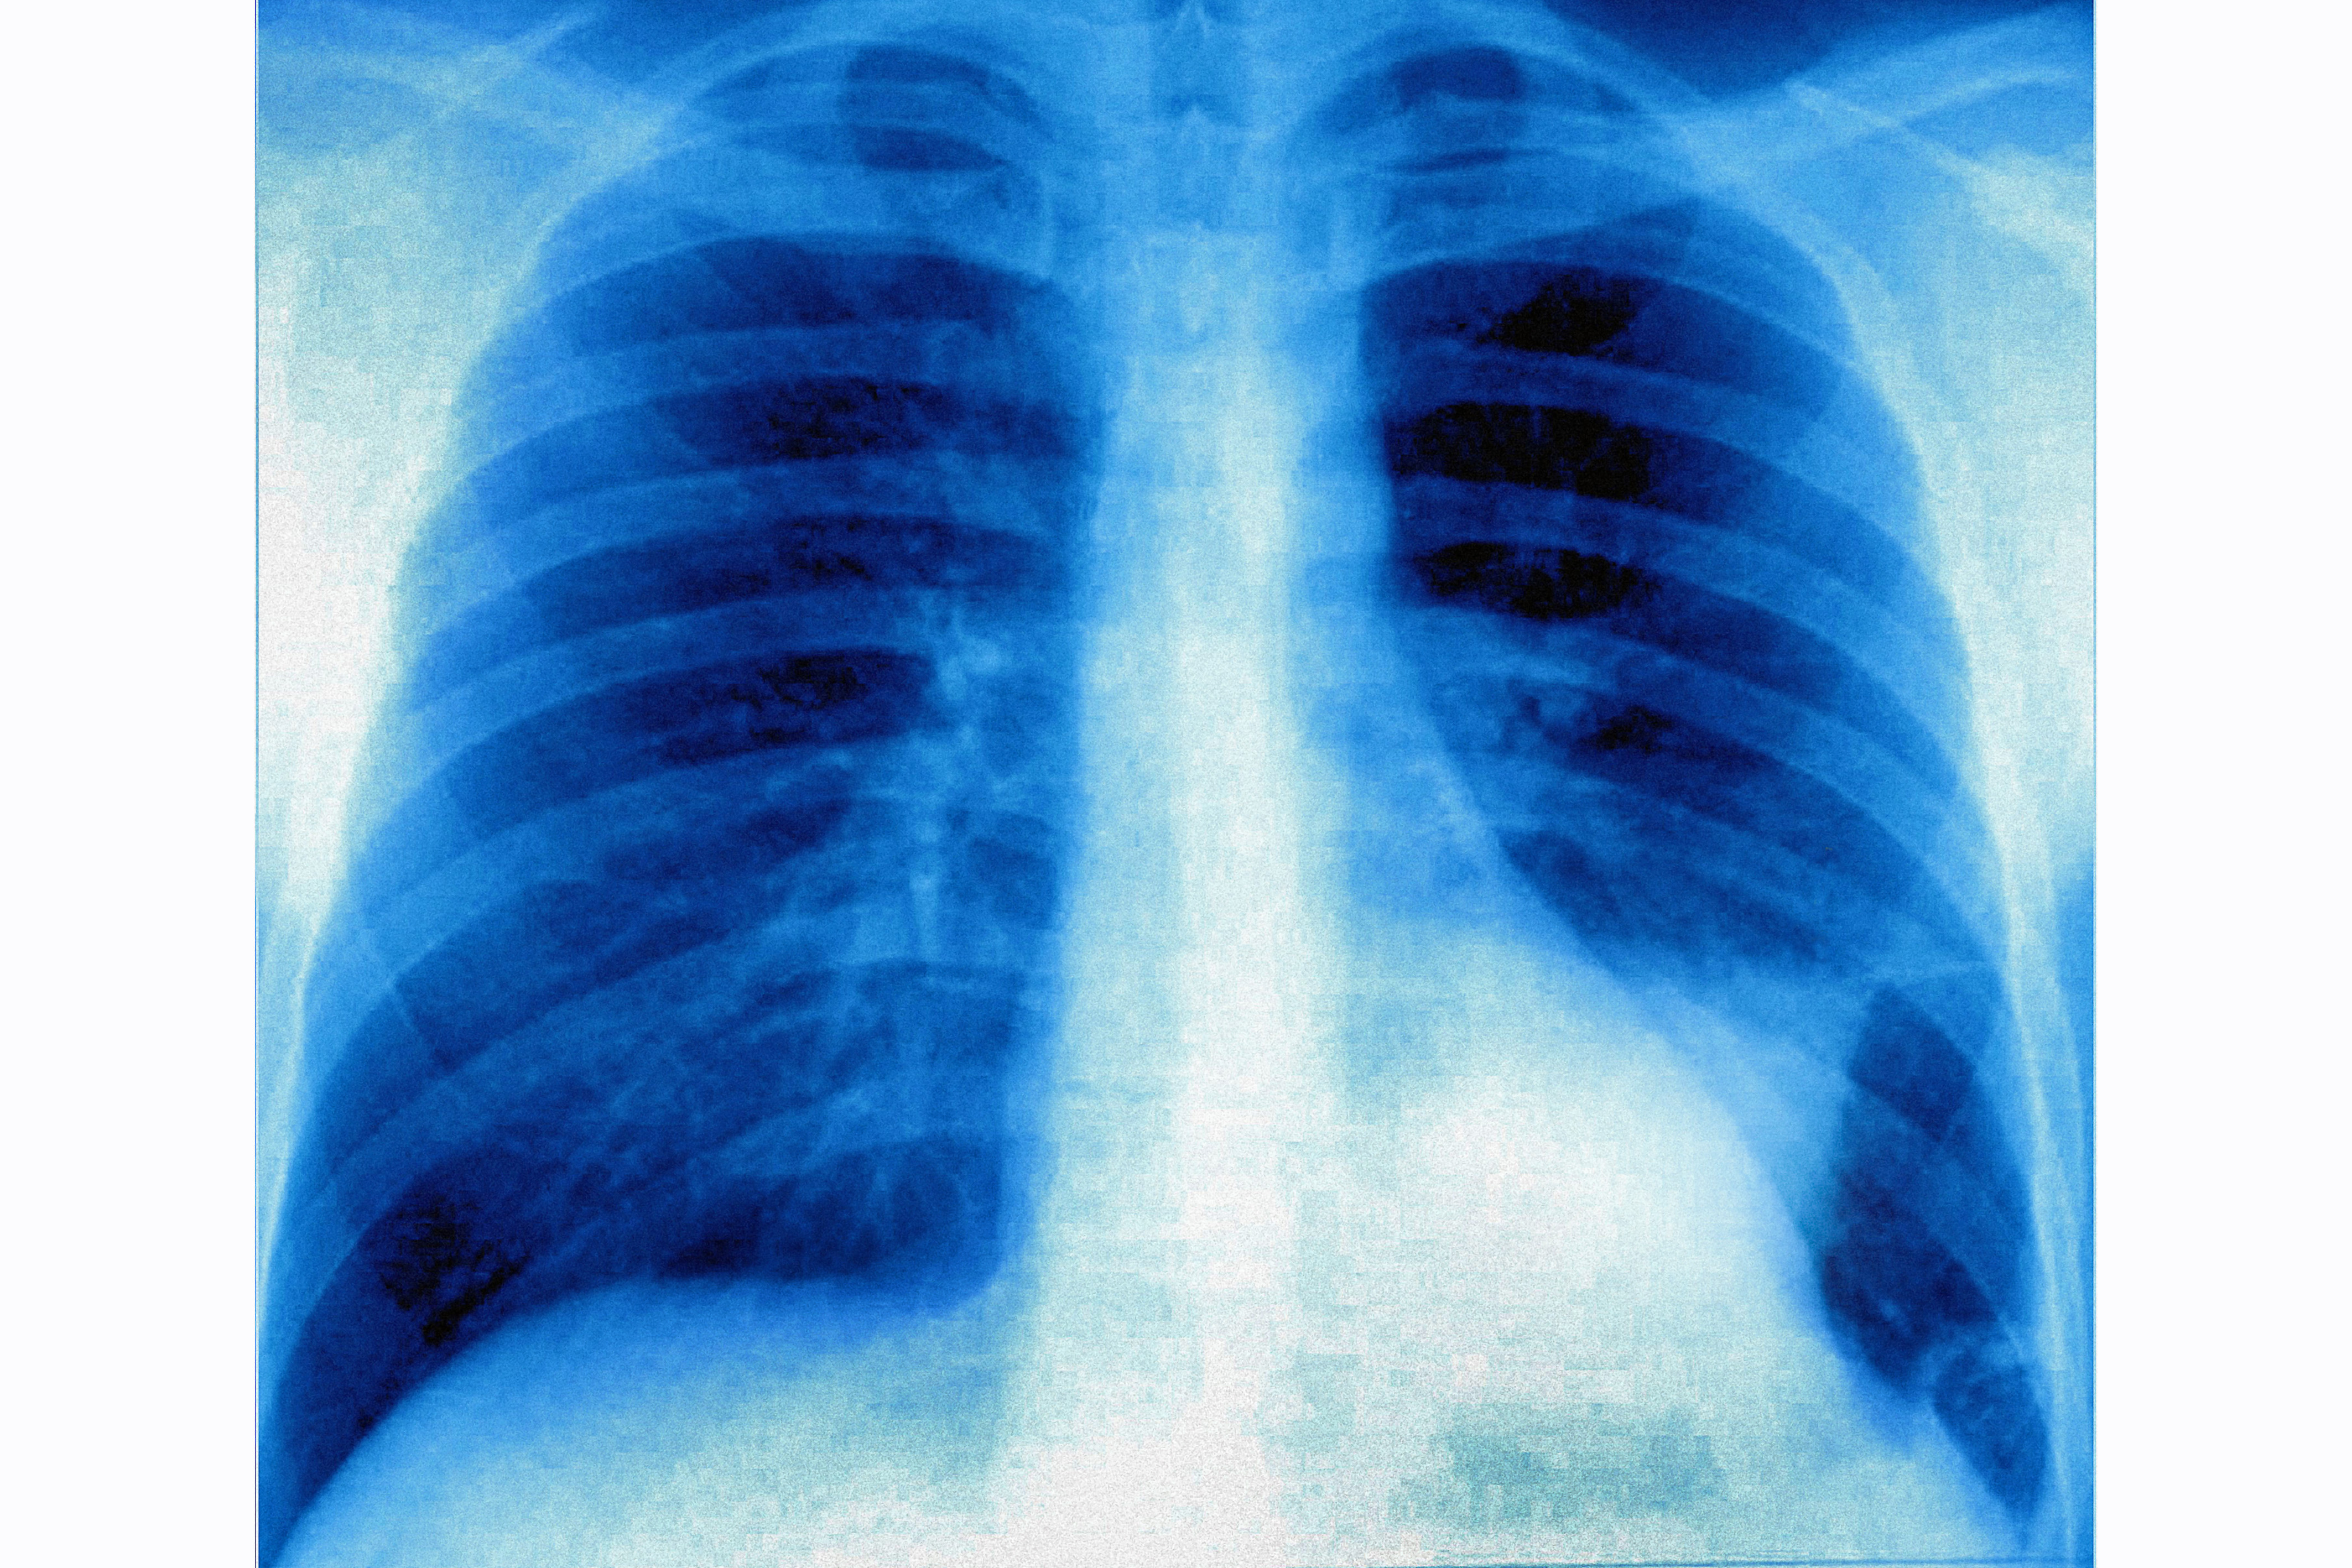

Lung cancer on the left pulmonary lobe, seen on a frontal x-ray of the chest. (Photo by: BSIP/Universal Images Group via Getty Images)

The findings suggest that "immediate reporting by radiographers significantly shortened the time to diagnosis by around 31 days, cutting usual diagnosis and waiting time by half".

Results also show that radiographer reports are comparable to consultant radiologists, supporting the use of trained radiographers to help increase reporting resources in the NHS.

“We know that the early, rapid and accurate diagnosis of lung cancer will help improve outcomes for patients,” he said. “By utilising the expertise of reporting radiographers we found that we could reduce the time to diagnosis by half by giving patients the results of their X-rays at the time they were taken, explaining the findings and arranging a CT chest scan, the next part of their journey."